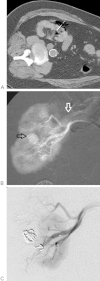

Although percutaneous ablation of small renal masses is generally safe, interventional radiologists should be aware of the various complications that may arise from the procedure. Renal hemorrhage is the most common significant complication. Additional less common but serious complications include injury to or stenosis of the ureter or ureteropelvic junction, infection/abscess, sensory or motor nerve injury, pneumothorax, needle tract seeding, and skin burn. Most complications may be treated conservatively or with minimal therapy. Several techniques are available to minimize the risk of these complications, and patients should be appropriately monitored for early detection of complications. In the event of a serious complication, prompt treatment should be provided. This article reviews the most common and most important complications associated with percutaneous ablation of small renal masses.